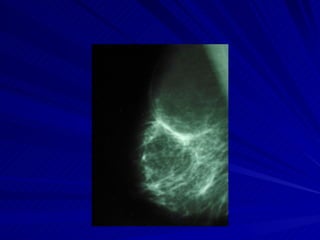

Cáncer de mama